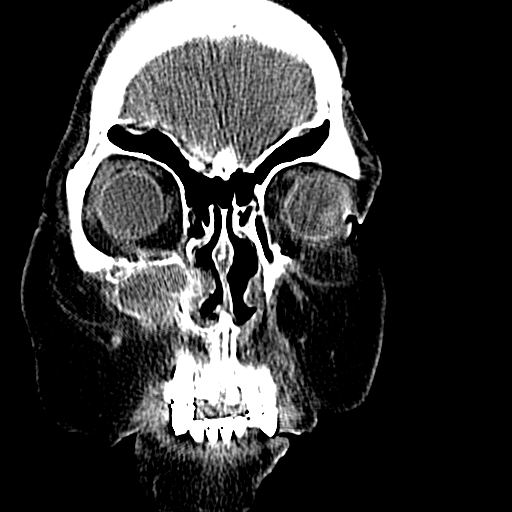

标题: CT19708:单侧上颌窦病变

老年患者,女。鼻塞多年。

考虑右侧上颌窦良性占位性病变,粘液囊肿可能性大;建议活检。

膨胀性生长,且骨质无破坏,说明时间久,良性;从密度,边缘看,内部还见坏死区,应该是实性肿瘤,定性,影像学无绝对的特异性

病灶密度很不均匀,骨壁膨胀中有断裂,考虑内翻乳头状瘤可能性大,粘液囊肿不排除

膨胀性生长,且骨质无破坏,说明时间久,良性;从密度,边缘看,内部还见坏死区,应该是实性肿瘤,定性,影像学无绝对的特异性,考虑内翻性乳头状瘤可能